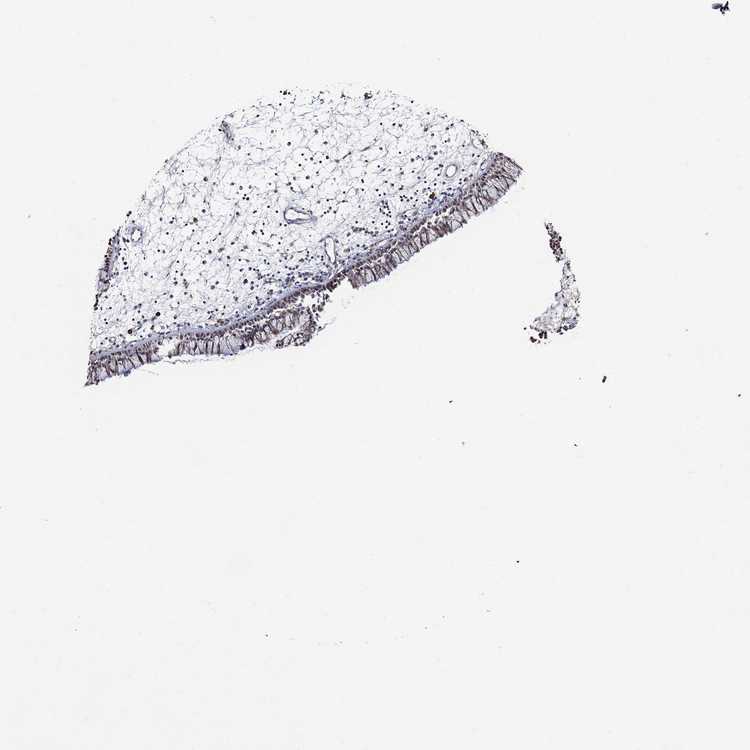

TISSUE PRIMARY DATA NASOPHARYNX Show tissue menu

NASOPHARYNX - Antibody stainingi

Antibody staining in the annotated cell types in the current human tissue is reported as not detected, low, medium, or high, based on conventional immunohistochemistry profiling in selected tissues. This score is based on the combination of the staining intensity and fraction of stained cells.

Each image is clickable and will lead to virtual microscopy that enables deeper exploration of all samples and also displays staining intensity scores, fraction scores and subcellular localization as well as patient and tissue information for each sample.

Antibody HPA059912Antibody HPA078559

Respiratory epithelial cells Not detectedMedium